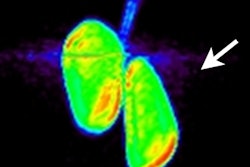

His group's objective was to create a deep-learning neural network that is capable of identifying patients with mild cognitive impairment or Alzheimer's disease based on the imaging appearance on FDG-PET and MRI. The model was based on Google's Inception V3 network architecture.

To create and test their deep-learning technique, the researchers started with data from PET brain scans of 982 patients from the Alzheimer's Disease Neuroimaging Initiative (ADNI). They also collected the same information from 110 patients in UCSF's PACS over the past 10 to 15 years.

Image preprocessing was performed over an entire volume of 2-mm isotropic MRI voxels and cropped to a 20 x 20 x 18-cm3 region centered on the brain. The entire volume was divided into 16 evenly spaced slices and placed into a 4 x 4 grid. The resulting map specifically focused on the inferior frontal lobes and temporal and occipital lobes, where atrophy is known as one cause of dementia.